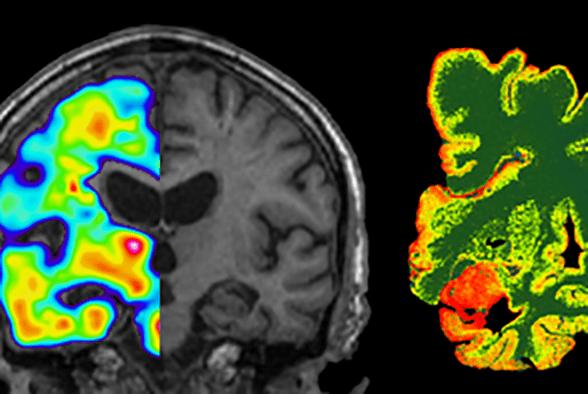

Foto: Selma Wolofsky, Institutionen för NVS.Neurogeriatrik